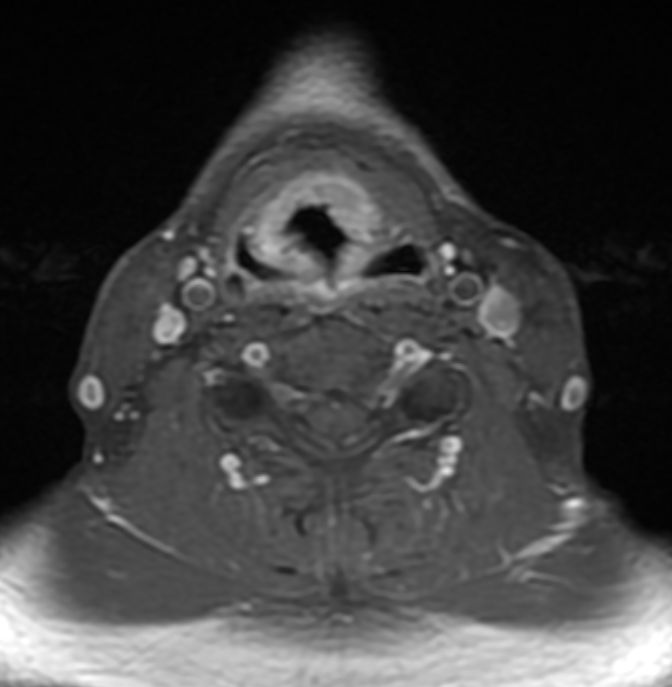

MRT: supraglottisch T3 No |

57-jähriger Mann mit langjährigem Alkohol- und Nikotinabusus. Seit 6 Monaten Schluckbeschwerden. Jetzt zunehmende Kachexie. MRT: Ausgedehntes supraglottisches Larynxkarzinom mit Schildkrorpel-Infiltration. Kehlkopfteilresektion mit ND. Histologie: unverhornendes Plattenepithelkarzinom, V0 R1 G1 - 2 Stadium post OP: pT3 pN0 (0/7) M0 | ||